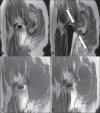

Soft tissue complications following hip arthroplasty may occur either in cases of total hip arthroplasty or in hip resurfacing, a technique that has become popular in cases involving young patients. Both orthopedic and radiological literatures are now calling attention to these symptomatic periprosthetic soft tissue masses called inflammatory pseudotumors or aseptic lymphocytic vasculites-associated lesions. Pseudotumors are associated with pain, instability, neuropathy, and premature loosening of prosthetic components, frequently requiring early and difficult reoperation. Magnetic resonance imaging plays a relevant role in the evaluation of soft tissue changes in the painful hip after arthroplasty, ranging from early periprosthetic fluid collections to necrosis and more extensive tissue damage.